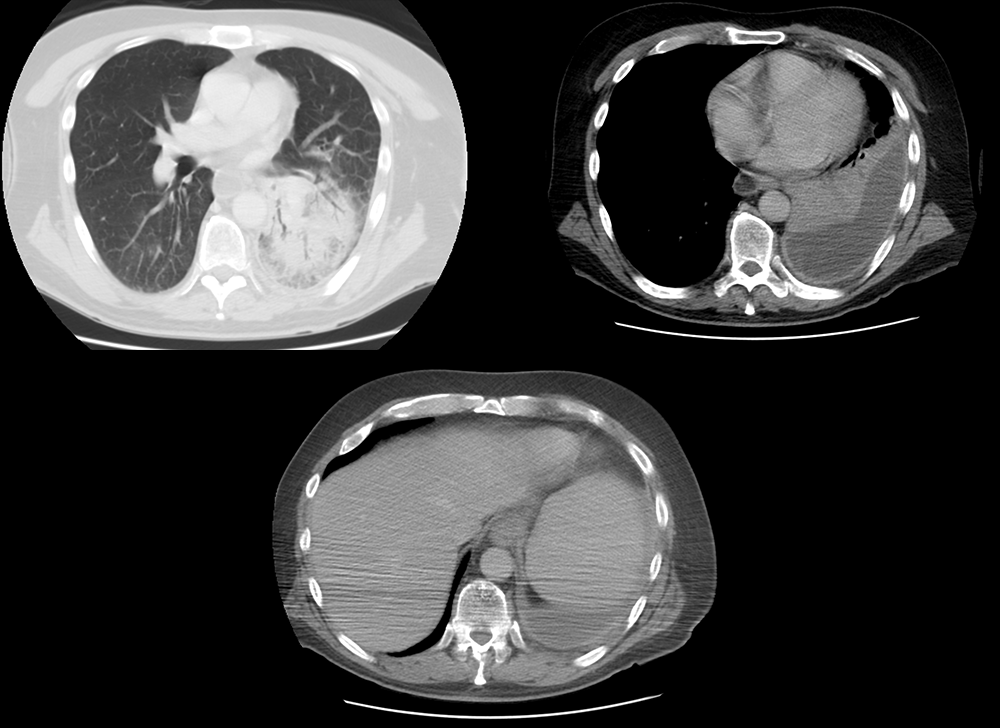

Chest CT

What best describes the findings on the Chest CT?

The lobar pneumonia with air bronchograms in the left lower lobe is apparent. The visceral and parietal pleura are thickened due to fibrin deposition and enhance due to vessel growth. This represents the “split pleura sign”.

View the full study if you'd like to like a look yourself

The CT findings strongly suggest a complicated pleural effusion or empyema.

The thickened and enhancing pleura on imaging suggest that this is a complicated paranepneumonic effusion or empyema.

Lessons Learned: In a complicated parapneumonic effusion, there is bacterial invasion in the pleural space. Therefore, the pleural fluid would have a positive gram stain, low pH (<7.2), and low glucose (<60). A parapneumonic effusion is considered an empyema when there is frank pus in the drained fluid. CT with contrast revealing thickened and enhancing pleura strongly suggest the presence of a complicated pleural effusion or empyema. Loculations can be present in both complicated parapneumonic effusions and empyema.